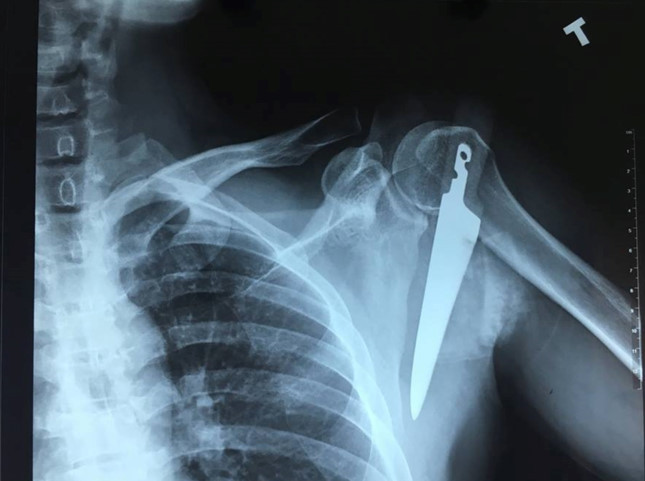

Hình ảnh phim chụp con dao đâm sâu vào vai trái bệnh nhân. (Ảnh: Bệnh viện cung cấp).

Báo Lao động đưa tin, ngày 13/2, Bệnh viện Việt Nam – Thụy Điển Uông Bí cho biết, ngày 8/2, anh L.T.T. (35 tuổi ở Uông Bí, Quảng Ninh) nhập viện với một con dao găm sâu vào vai trái.

Chia sẻ với Zing.vn, các bác sĩ điều trị thông tin, người bệnh nhập viện với một con dao găm ngập cán vào vùng vai trái ngay dưới xương đòn, mất nhiều máu.

Vị trí này gần ngay các động mạch lớn và đám rối thần kinh cánh tay. Nếu không được tiến hành phẫu thuật cấp cứu kịp thời, người bệnh sẽ phải đối mặt với nguy cơ như chảy máu nhiều, mất máu, nhiễm trùng, có thể tử vong.

Con dao được lấy ra sắc, nhọn có chiều dài hơn 20 cm. Hiện tại sức khỏe người bệnh ổn định, vết mổ khô và sẽ được xuất viện trong vài ngày tới.